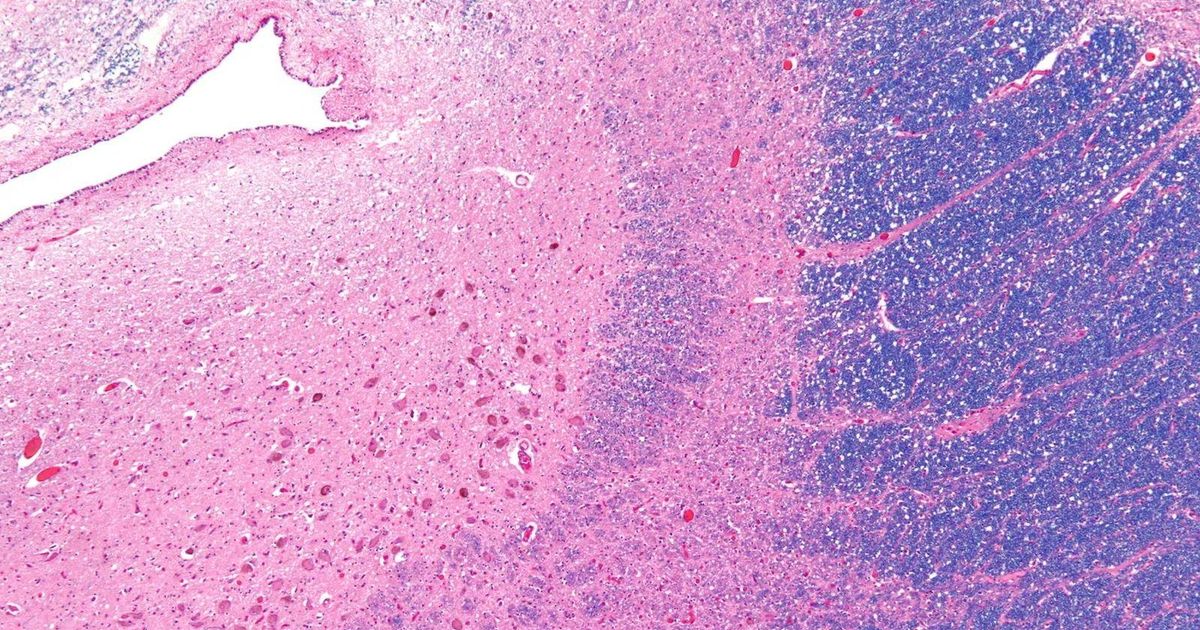

O locus coeruleus assume coloração azul viva com a produção do neurotransmissor norepinefrina Crédito: Wikimedia Commons/ Nephron

Esta descrição é literal. Os neurônios do locus coeruleus são tingidos em cor de safira devido à produção de um neurotransmissor específico, chamado norepinefrina.